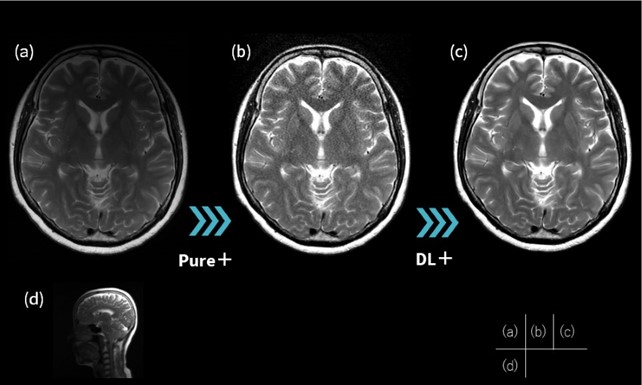

3. AIR™ Recon DLを活用した頭部DWIのthin slice撮像

頭部DWIでは、脳実質の信号が高いことから他部位に比べ高分解能で撮像されることが多いが、ARDLを用いる事で更なる高分解能化が可能と考える。DWIにて高解像度化を図る場合、面内分解能を高くすると周波数マトリックスの上昇に伴い歪みの影響が大きくなり、アーチファクト増大を招く2)。一方で、スライス厚を薄くすることでパーシャルボリューム効果の影響を減少させ、歪みの影響を増大させず解像度を向上させることができる3)。Fig.3に急性期ラクナ梗塞の臨床例を示す。面内分解能を高くした撮像条件(a)(c)では小さな梗塞巣を検出することができないが、スライス厚を薄くする(b)(d)ことで病変部が明瞭となった。このように、ARDLを活用した頭部DWIのthin slice撮像は、SNRを担保しつつ歪みの影響を増大させることなく尖鋭度を向上させる有益な手法であり、臨床的意義の高い画像が可能となった。また、本法の2D thin slice撮像は他シーケンスにも応用可能であり、スライス数増加に伴うSAR上昇が懸念される3T装置よりも1.5T装置での活用が有効である点4)も、Voyagerの利点と言える。

VoyagerMR30_ube04.jpg

Fig.3 急性期ラクナ梗塞における面内高分解能撮像 とthin slice撮像の描出能の比較

(a)(c) slice thickness:5mm, matrix:256*256 (b)(d) slice thickness:3mm, matrix:128*256